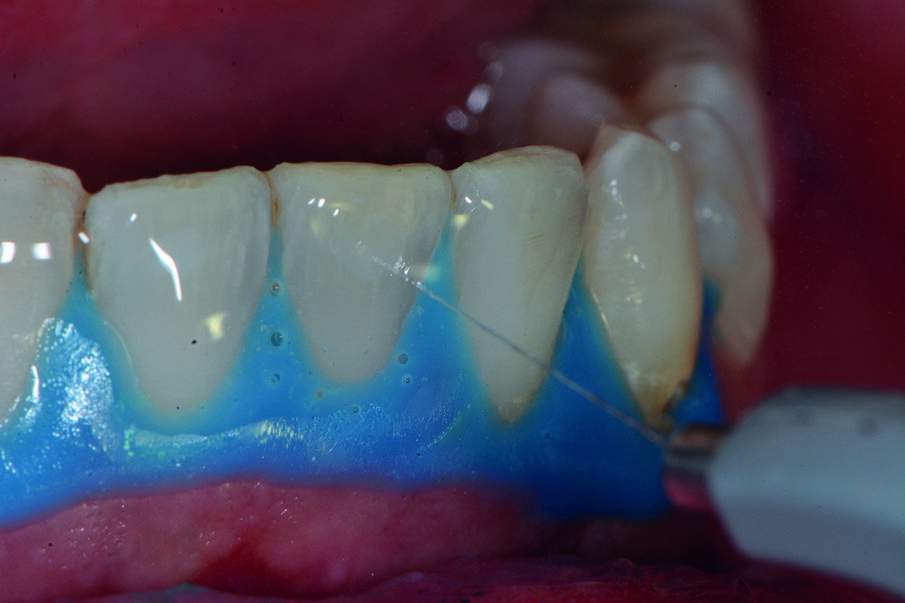

Prima del trattamento abbiamo applicato un rilevatore di placca alla fluoresceina Plac-o-Tect (Directa) per evidenziare la topografia della presenza di biofilm batterico nel cavo orale. Osserviamo la topografia del biofilm batterico presente e condividiamo con il paziente i siti più ritentivi di biofilm batterico in modo da avere una comunicazione non verbale del rivelatore, utile per il rinforzo motivazionale del paziente con l’obiettivo di migliorare l’efficacia dell’igiene orale domiciliare (Fig. 3).

La metodica D-BIOTECH è applicabile nella terapia parodontale non chirurgica, come approccio clinico meccanico o manuale nel deplaquing e nel debridment. Tale approccio permette di eseguire un lavoro minimamente invasivo poiché l’operatore può strumentare con polishing selettivo, airpolishing, ablatori o strumentazione manuale seguendo esclusivamente la topografia del biofilm batterico, poiché intercetta visivamente i siti più a rischio di infiammazione attraverso la colorazione del rivelatore.

La comunicazione non verbale visiva di questo approccio clinico nuovo permette un lavoro sicuramente più ergonomico per l’operatore, che sceglierà lo strumento o la tecnica operativa più performante per strumentare unicamente dove sono presenti biofilm batterico e discromie acquisite (Fig. 5).